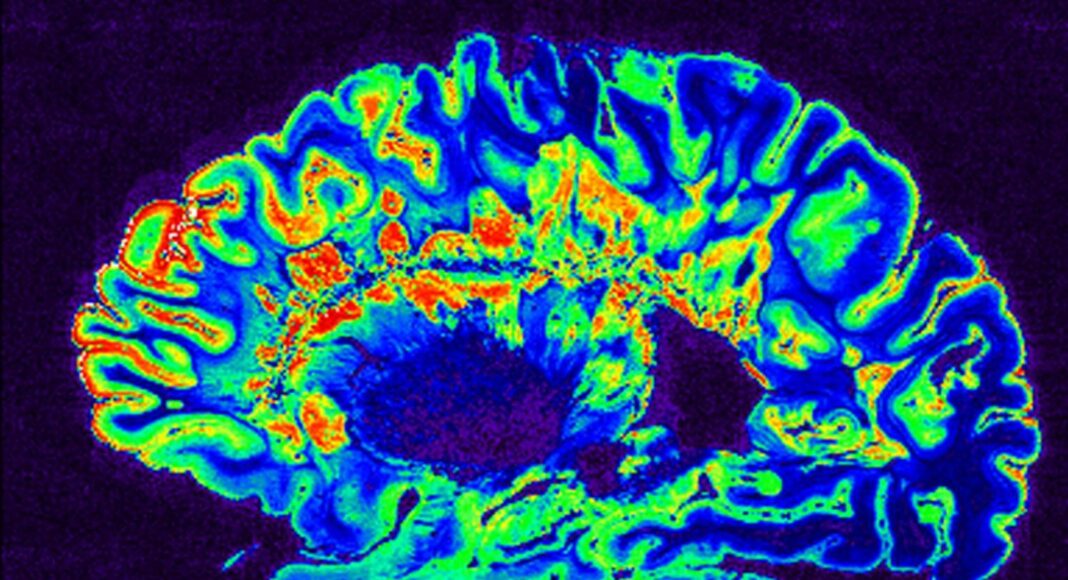

Η ερευνητική ομάδα χρησιμοποίησε τεχνητή νοημοσύνη (ΤΝ) προκειμένου να αναλύσει τομογραφίες εγκεφάλου, καθώς και τα επίπεδα των νευροϊνιδίων ελαφράς αλύσου (NfL) στον ορό (serum neurofilament light chain – sNfL), ενός αιματολογικού δείκτη βλάβης των νευρικών κυττάρων.

Ο ένας υποτύπος ονομάστηκε «πολλαπλή σκλήρυνση πρώιμης sNfL» και παρουσίαζε υψηλά επίπεδα του εν λόγω αιματολογικού δείκτη ήδη από τα αρχικά στάδια της νόσου, σε συνδυασμό με βλάβες στο μεσολόβιο — περιοχή του εγκεφάλου κρίσιμη για τη σκέψη, τη μνήμη και τον συντονισμό των κινήσεων.

Ο δεύτερος υποτύπος, ο οποίος ονομάστηκε «πολλαπλή σκλήρυνση όψιμης sNfL», παρουσίαζε μεταγενέστερη αύξηση των επιπέδων sNfL και συνδεόταν με «πρώιμη απώλεια όγκου στον φλοιό και σε τμήμα της φαιάς ουσίας», όπως αναφέρουν οι συγγραφείς στη μελέτη τους που δημοσιεύθηκε στο επιστημονικό περιοδικό Brain.